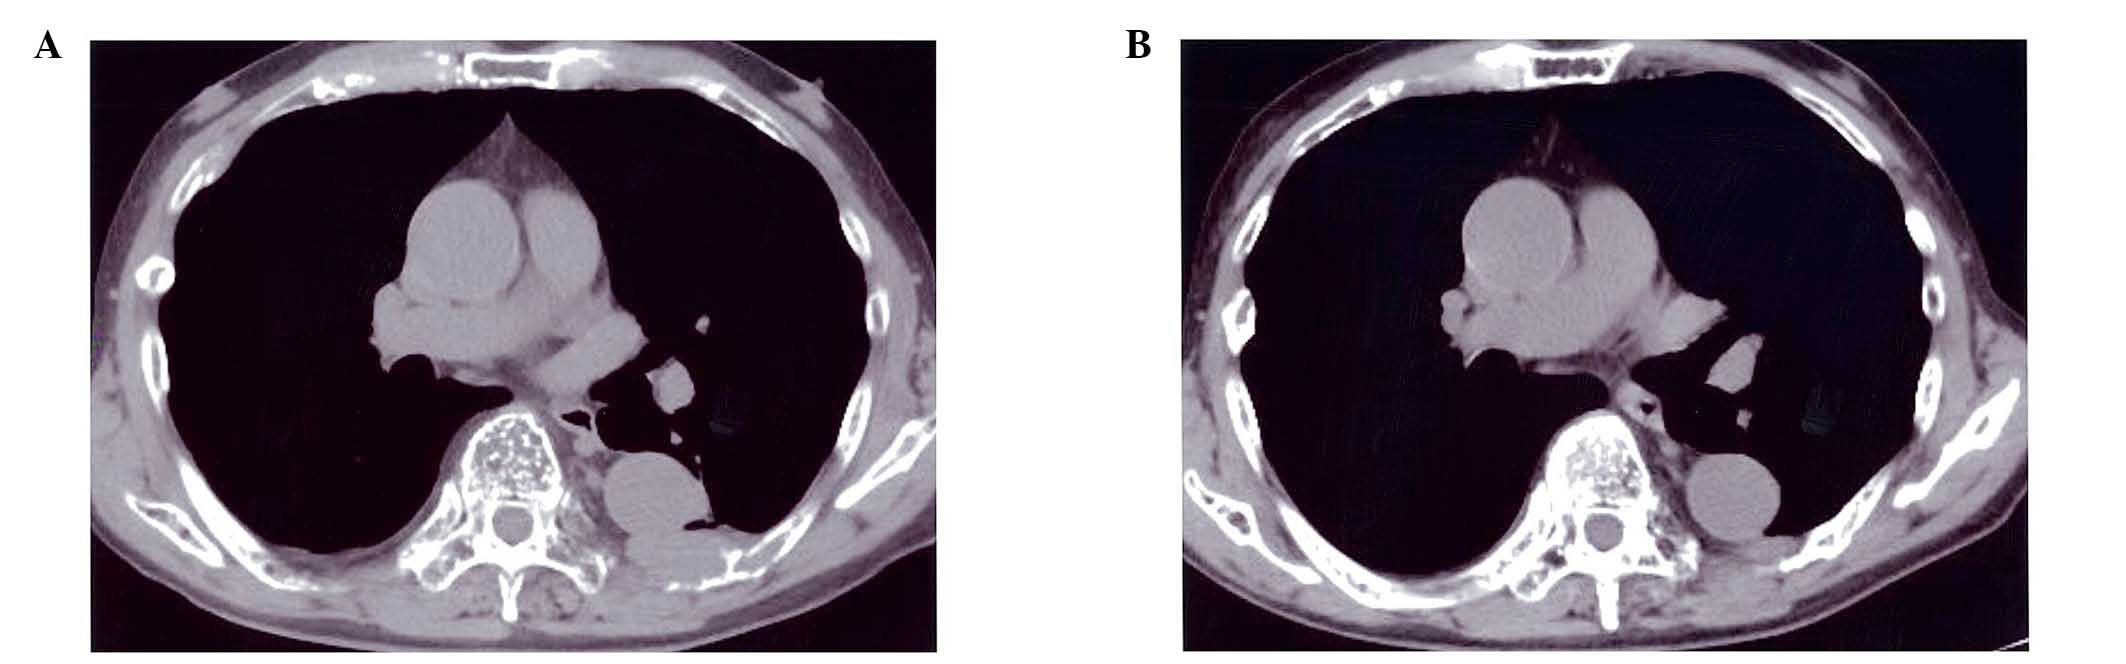

A 72-year-old Japanese male was diagnosed as having monoclonal gammopathy of undetermined significance and was followed up without therapy. Three years later, the patient progressed to symptomatic multiple myeloma. Melphalan + prednisolone was administered as first‑line chemotherapy for ~6 years. Since the patient was judged to exhibit refractory multiple myeloma, he subsequently received radiation therapy on the lumbar spine. The patient was enrolled in a clinical trial and received lenalidomide + lowdose dexamethasone (Rd) therapy. The patient achieved very good partial remission following four cycles of Rd. At this time, large granular lymphocytes (LGLs) increased to 25‑40% of peripheral blood leukocytes, however, the LGLs were present in the blood (~8%) prior to lenalidomide treatment. By flow cytometry of surface antigens, it was revealed that the LGLs were positive for cluster of differnetiation (CD)2, 7, 8, 16, 56, and 57, and human leukocyte antigen‑D related, however, were negative for CD3, 4 and 5, suggesting that these LGLs predominantly exhibited an natural killer (NK) cell phenotype. T‑cell receptor β gene rearrangement was not detected by polymerase chain reaction. A 51Cr release assay was performed to investigate whether the NK cells actually possessed activity. A low level of M protein was sustained for ~15 months. This implied the enhancement of immune activation during lenalidomide treatment. The present case study suggested that LGL cells induced by lenalidomide may contribute to long‑term restraint of myeloma cells. This immune system component may contribute to disease control.

Figure 1